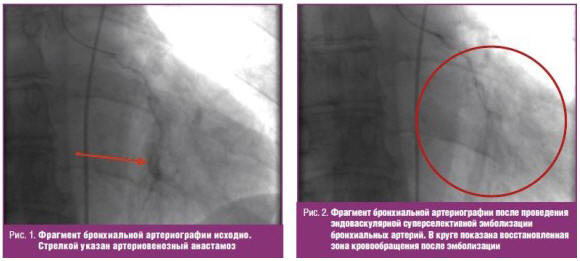

23.09.2015 г. При артериографии бронхиальных артерий выявлены аневризматические

изменения в области сосудов нижней доли правого легкого и выраженные

артериовенозные анастомозы в области нижней доли левого легкого (рис. 1), что

потребовало в дальнейшем проведения эндоваскулярной эмболизации этих артерий. 25

сентября 2015 г. проведена эндоваскулярная суперселективная эмболизация

бронхиальных артерий (рис. 2). Послеоперационный период протекал гладко, без